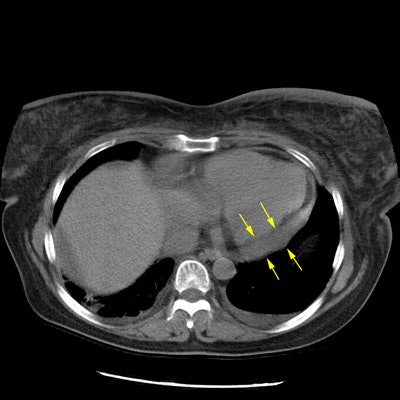

Earlier interstitial lung disease:

The case below is an example of interstitial lung disease at an earlier stage in a patient with a history of breast cancer (and a prior right mastectomy). There are patchy areas of fine subpleural "lace-like" intralobular interstitial thickening. Thickened interlobular septa are also seen, as is honeycombing- particularly in the posterior costophrenic sulci. The fibrosis associated with interstitial lung disease produces architectural distortion which is not seen in patients with lymphangetic metastases.